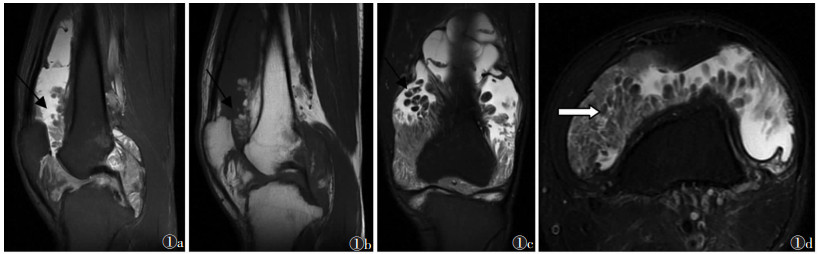

| 图 1 男, 31岁, 树枝状脂肪瘤 图1a~1d 分别为矢状位FS-T2WI、矢状位T1WI、冠状位压脂T2WI及横断位FS-T2WI图像, 滑膜肥厚呈树枝或海草样弥漫性增生, T1WI呈等信号、FS-T2WI等或稍高信号, 增生肥厚滑膜内见多发类圆形或类椭圆形与皮下脂肪层一致的T1WI高信号、FS-T2WI低信号 |

2.2 滑膜病变形态及MRI信号5例树枝状脂肪瘤患者滑膜肥厚、呈树枝或海草样弥漫性增生, T1WI呈等信号、FS-T2WI等或稍高信号, 增生肥厚滑膜内见多发类圆形或类椭圆形、与皮下脂肪层一致的T1WI呈高信号、FS-T2WI低信号(图 1)。10例色素沉着绒毛结节滑膜炎滑膜肥厚呈绒毛或结节样弥漫增生, T1WI呈等或低信号、T2WI呈低信号, 增强扫描明显不均匀强化; 增生滑膜内可见T1WI及FS-T2WI均呈低信号的含铁血黄素结节, 增强扫描在强化滑膜衬托下呈低信号(图 2a~2c)。